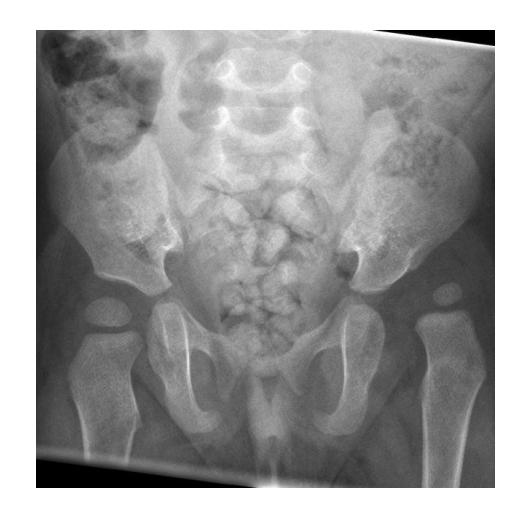

How to Read an X-Rayof Pediatric Hip